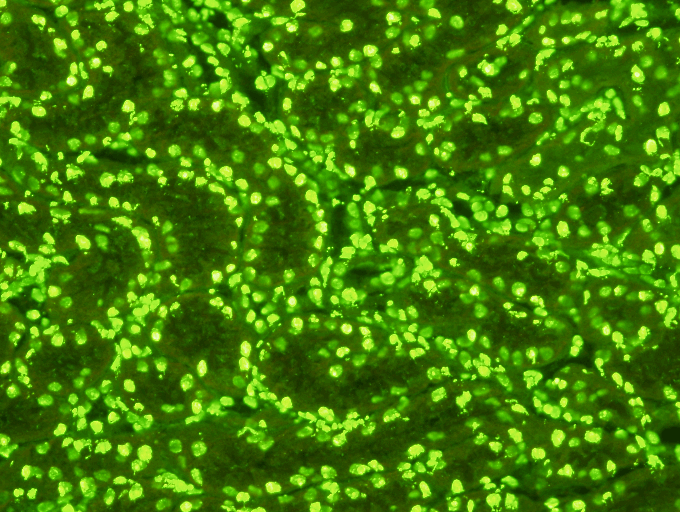

Anti-nuclear Antibody (HEp2 Cell Culture) Test Kit  Indirect Immunofluorescence Assay is a qualitative or semi-quantitative assay for the in vitro diagnostic detection of Anti-nuclear Antibodies in human serum on human epithelial cells (HEp2). &nbsp

Anti-nuclear Antibody (HEp2 Cell Culture) Test Kit

Indirect Immunofluorescence Assay is a qualitative or semi-quantitative assay for the in vitro diagnostic detection of Anti-nuclear Antibodies in human serum on human epithelial cells (HEp2).  The test is intended as an aid in the diagnosis of SLE and connective tissue diseases.

1060L  70 Test Kit

1120L  140 Test Kit

H300L 350 Test Kit